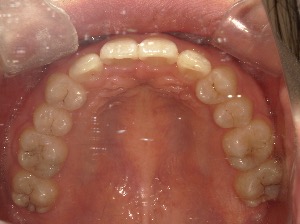

after

患者さんの年齢 20代 女性 症状 ガタガタを治したい 治療内容 マウスピース矯正治療 費用 90万(税抜) 治療期間・回数 治療期間2年、通院回数10回 メリット 笑顔が綺麗 デメリット・リスク 期間がかかることがある - マウスピース矯正